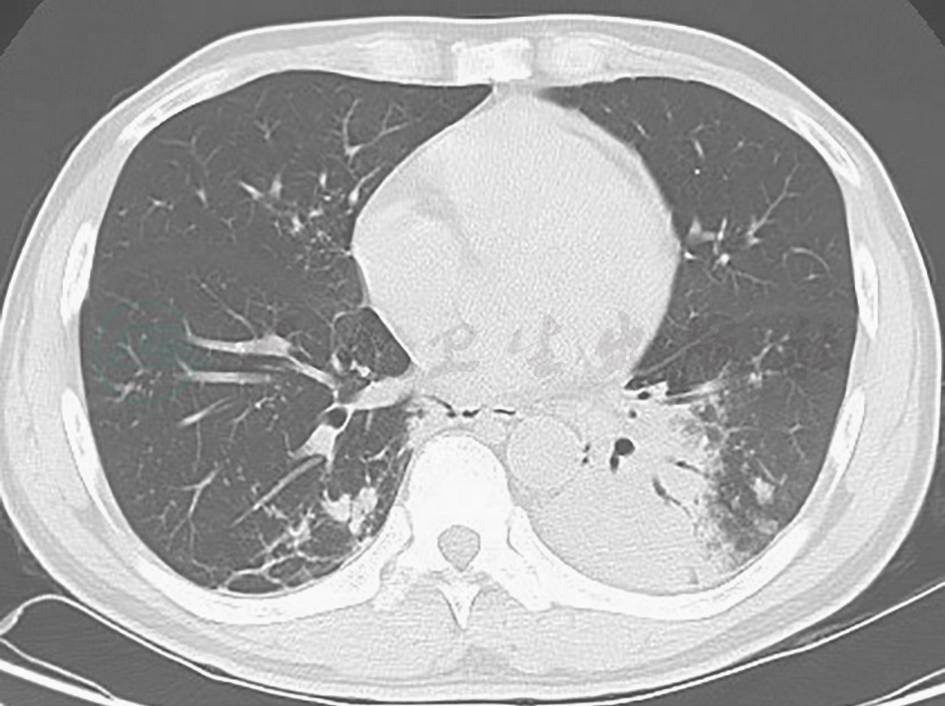

明确诊断后,考虑到患者双肺多发病变,无手术指征,采取停用前述抗感染药物,给予甲泼尼龙,患者未再发热,咳嗽、咳痰、胸痛症状缓解,但复查胸部CT仍显示病变进一步发展(图13)。

图13 激素治疗18天后复查胸部CT表现

胸部CT可见双肺病灶进一步增多,以结节和团块状实变为主

IMT的临床及影像学表现无特异性。80%病例的胸部影像学表现为一个边界规则的孤立肿块,位于支气管内,可伴有阻塞性肺炎和肺不张。本例患者表现为斑片状实变影。激素治疗无效,胸部CT显示病灶进展,提示患者病情未得到控制,可能还需要加用免疫抑制剂等。